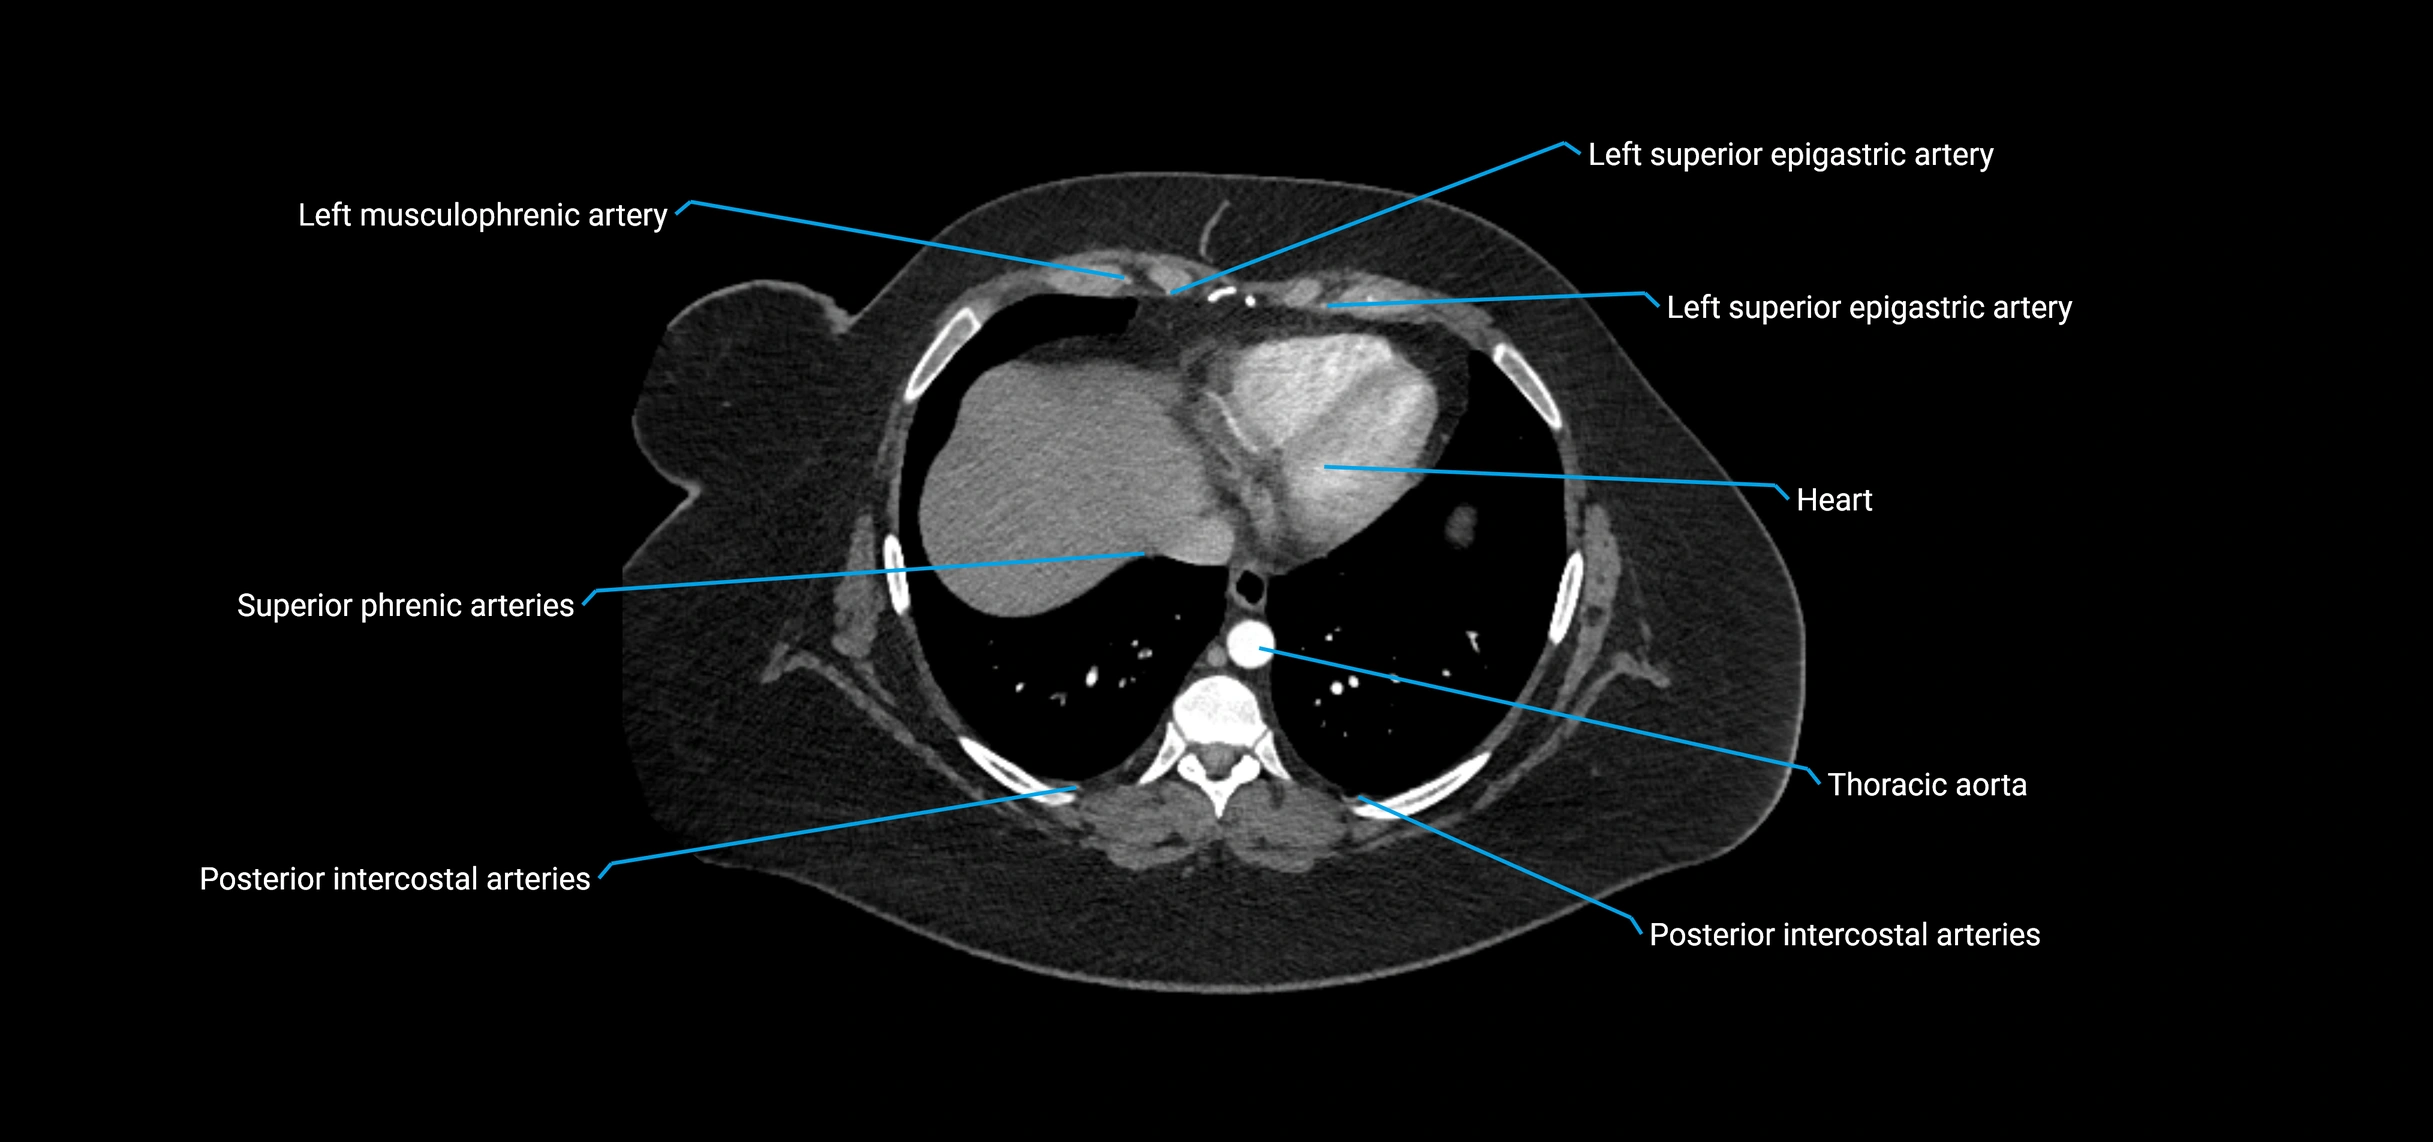

Contrast-enhanced CT (CTA):

• Gold standard for abdominal aortic imaging

• Provides excellent detail of lumen, wall, aneurysm, thrombus, and branch vessels

• Multiplanar and 3D reconstructions help in aneurysm measurement, stent graft planning, and dissection evaluation

• Detects acute rupture, traumatic injury, or occlusion with high sensitivity